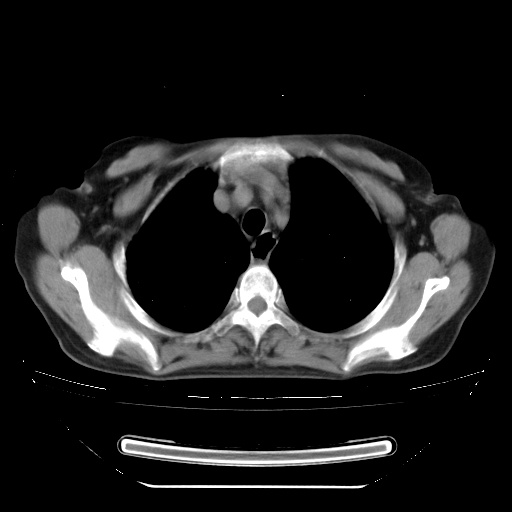

患者女性,72岁,慢性咳嗽3月余,曾抗炎治疗无效果,最近抗结核治疗约半月余,症状缓解。

ct示两肺粟粒状病灶,以两肺上叶尖后段及下叶背段分布为主;首先考虑结核。请战友们分析。

考虑 1 弥漫性泛细支气管炎, 2 结核不除外/.  有小叶中心结节 和 树芽征!!

两肺内病灶呈小结节状和树芽状,纵膈的肿大的淋巴结密度不均匀,并见有钙化,考虑为两肺结核可能更大些。

两肺内病灶呈小结节状和树芽状,纵膈的肿大的淋巴结密度不均匀,并见有钙化,多形态病灶,考虑为两肺结核,肝内考虑小囊肿。

支持亚急型粟粒性结核

考虑两肺播散性肺结核(亚型),纵隔淋巴结结核。